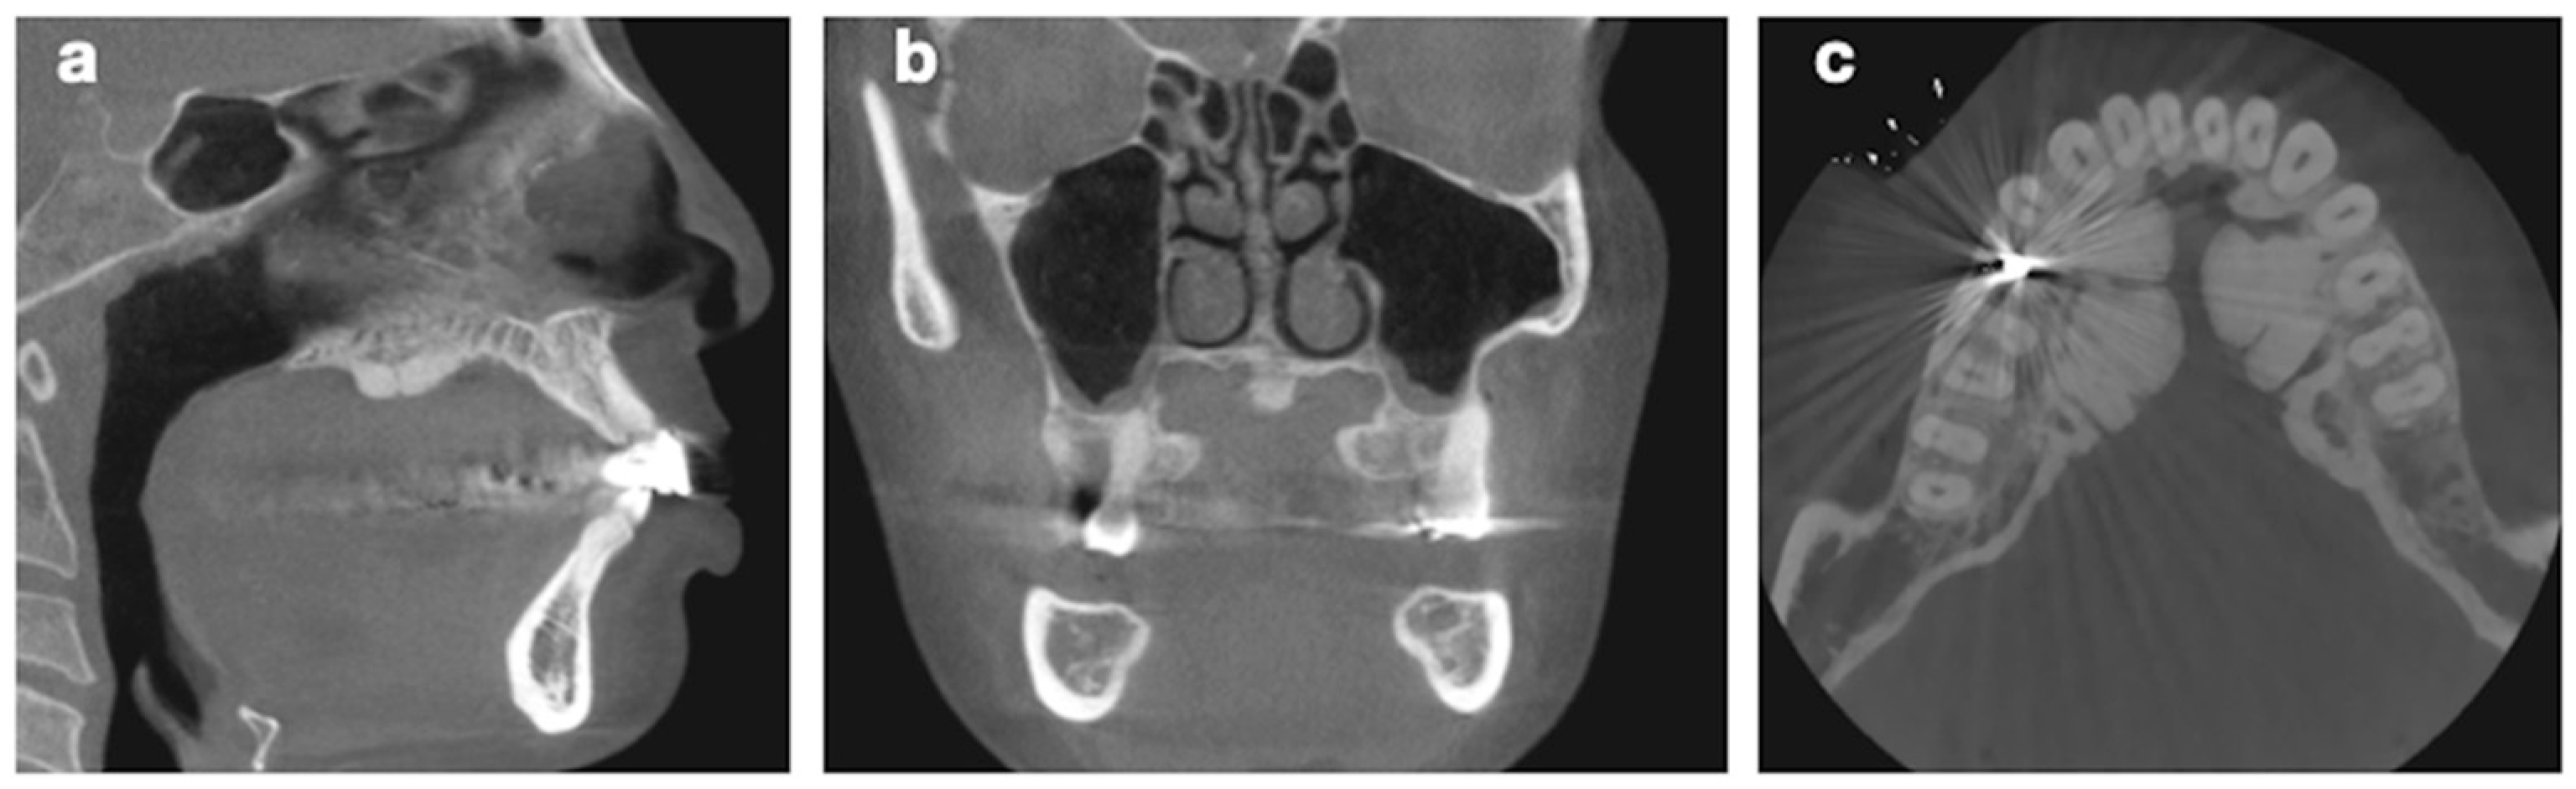

The University of Mississippi Medical Center School of Dentistry (UMMC SOD) patient archives were used in this retrospective study. Intraoral photographs, full-mouth series (FMS), panoramic radiographs, and cone-beam computerized tomography (CBCT) images from the clinic’s database of patients treated at UMMC SOD between January 2018 and May 2021 were examined in detail. Patients older than 18 years of age and with oral tori findings were included in the study (Figure 1 and Figure 2). A code in EPIC was also used to find patients with tori in the patient database. Intraoral photographs typically show the presence of bony growths along the palatal or mandibular areas, appearing as well-defined nodular or sessile projections. On panoramic radiographs, oral tori are identified as radiopaque, well-defined masses located in the maxillary or mandibular arches. The presence of these masses on CBCT scans provides further detail, revealing the exact location, size, and shape of the tori, which helps differentiate them from other bony lesions or exostoses. Radiographically, tori are characterized by dense cortical bone, often without significant trabecular involvement, and are seen as non-expansile, stable structures. Patients showing these findings through the various imaging modalities were included for evaluation in the study. The age, gender, and ethnic origins (Caucasian, African-American, or Asian) of the patients included in the study were recorded. In addition, the localization of the anatomical formations was evaluated, including the jaw in which the relevant anatomical formation was localized (localized only in the maxilla, only in the mandible, or in both). All protected health information was anonymized before the data were compiled.

Figure 2. CBCT cross-section images of patients. (a) CBCT sagittal section image of patient with maxillary tori. (b) CBCT coronal section image of patient with maxillary tori. (c) CBCT axial section image of patient with mandibular tori.